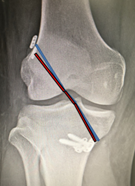

手術方法は、膝関節を構成する大腿骨と脛骨の最適部位に関節鏡を用いて細いトンネルを作製し、そこに採取した自分の組織を通し上端・下端を金具で固定します。採取する組織はハムストリングと言われる膝屈筋腱または膝蓋腱を使用します。膝屈筋腱を用いた場合は膝蓋腱を用いた場合よりスポーツ復帰まで長期間を要し(膝屈筋腱:9か月、膝蓋腱:6か月)、一方で膝蓋腱を用いた場合は膝前部の疼痛が残存することが多く、症例に応じて使い分けます。

採取した膝屈筋腱を処置したもの 術後レントゲン画像